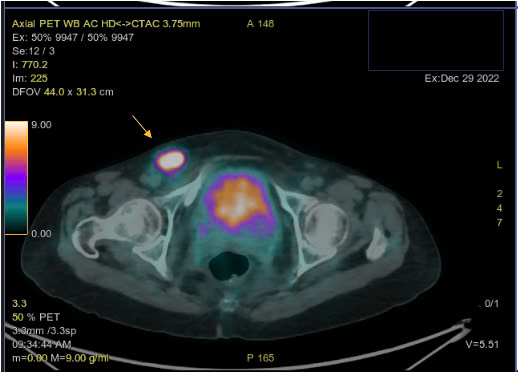

Hình ảnh PET/CT với F18-FDG đánh giá giai đoạn trước điều trị:

Hình 1. Hình ảnh tăng chuyển hóa FDG ở nhiều vị trí hạch trên và dưới cơ hoành và các cơ quan khác ngoài hạch

Hình 3. Hình ảnh hạch bẹn kích thước lớn tăng chuyển hóa FDG

– Hình ảnh hạch cổ 2 bên, hạch trung thất, hạch ổ bụng, hạch bẹn 2 bên tăng chuyển hóa FDG hướng tới ác tính.